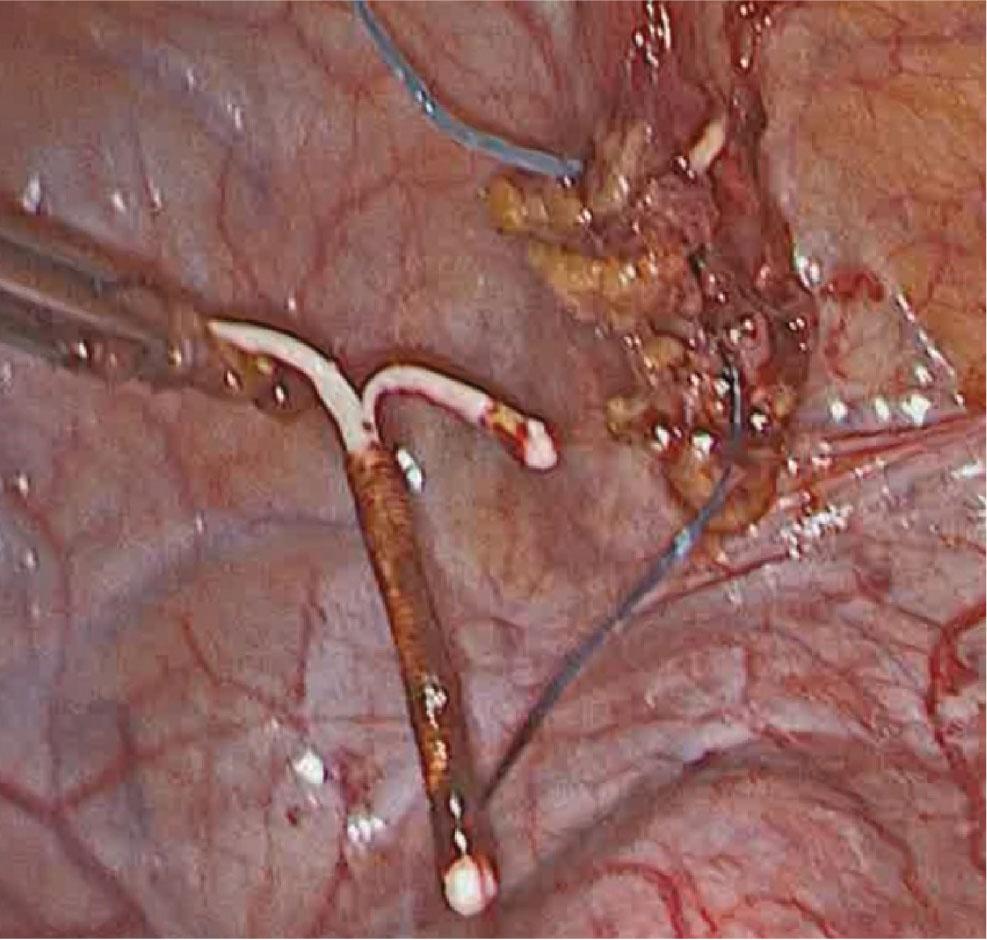

At surgery, the uterus was found to be intact (no visible evidence of perforation). The IUD turned out to be localized intraperitoneally, adherent to the urinary bladder dome and its superior surface by omental adhesions (Fig. 2). This location was in line with the findings from the computed tomography. A step-by-step atraumatic laparoscopic freeing of the device from the omental and urinary bladder adhesions enabled its final removal (Fig. 3). No blood loss was observed. The patient was discharged on the second postoperative day in a good general condition.